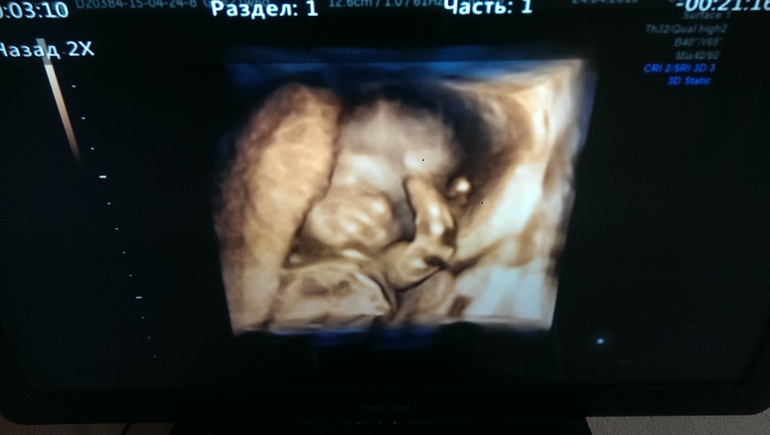

УЗИ, КТГ, доплерНа день рождения мужу решила подарить мужу поход на 4д узи :) Чтобы наконец познакомился с дочкой, пиночками радовать она его не спешит :) Узист сказал, что девочки обычно закрываются ручками всячески, но попросил ее папе в честь др показаться :)) Моя девочка папу порадовать решила как следует! Улыбалась, лежала нога на ногу, ротик открывала! Показала образцовый "фейспалм", позу мыслителя, пуповиной поиграла :) Ну и подтвердили, что 100% доча, что все у нее хорошо, весит 464г уже! Узист-мужчина так мило радовался с нами каждой ее улыбке, каждой красивой позе, впечатления отличные :) Муж довольный! Сидел улыбался :)Делали в Парацельсе на Большакова, если землячкам интересно :) Ну и пара фоток (пришлось включать на иксбоксе диск, сидиром отказался воспроизводить диски) :)